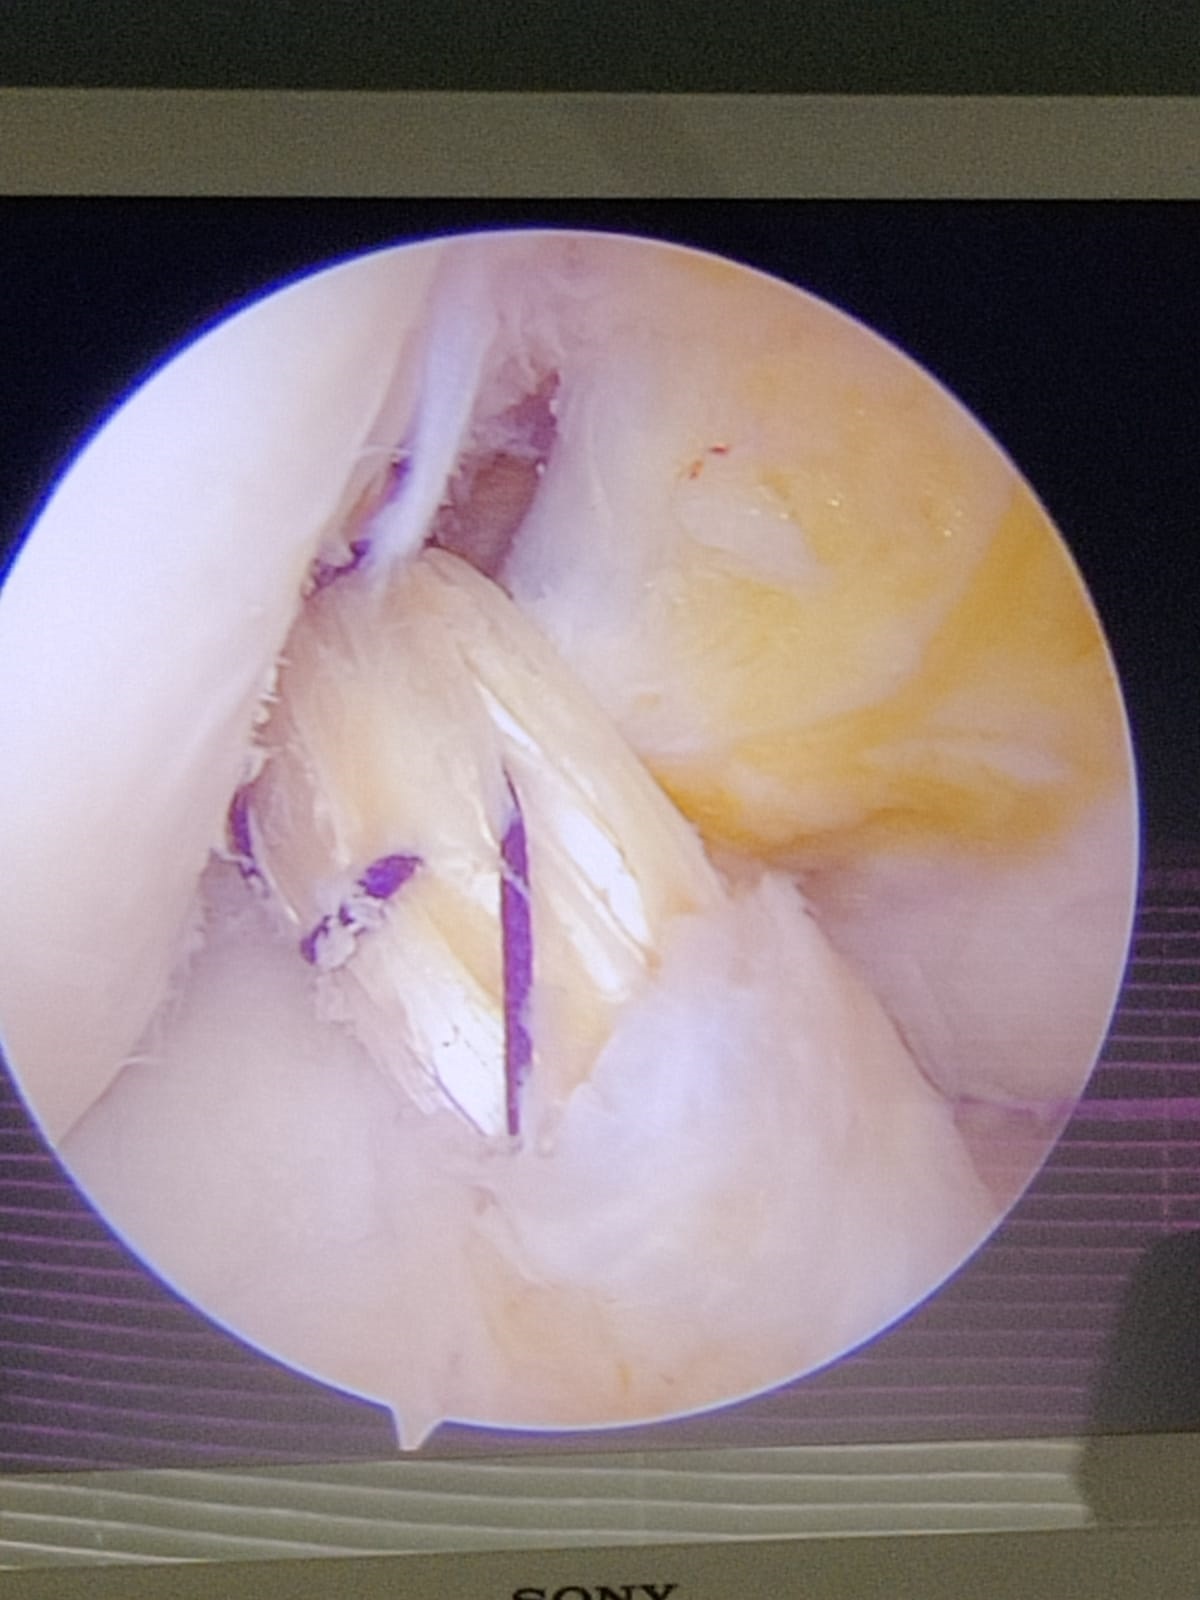

Knee arthroscopy is an important therapeutic procedure for treating knee disorders of various types. It is a surgical procedure which undertakes a small incision making and insertion of small camera called as arthroscope into the knees. Insertion of the arthroscope helps in observing the inside view of the joints on the screen of computer. It helps in identification of all knee problems. In some cases, problems knee can be corrected with the help of small instrument within the arthroscope.

Small incisions will be made by the surgeon at the start of knee arthroscopy. After this, saline or sterile salt water is pumped inside for expanding the knees. An arthroscope enters inside one of the incisions made and a surgeon can see inside with the help of camera attached. After identification of problem inside the knees, insertion of small instruments is carried out by the surgeon for correcting the trouble.